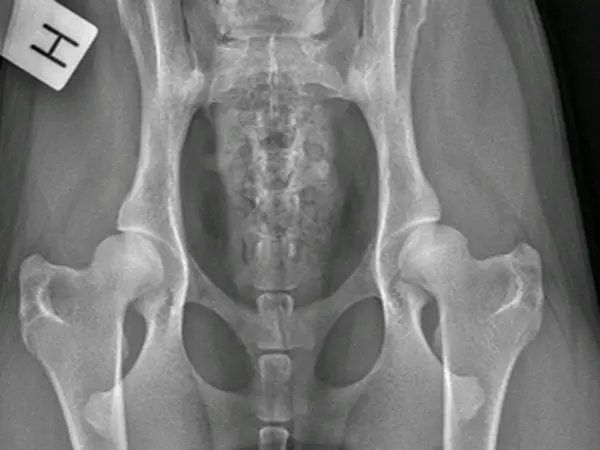

Vores smådyrshospital i Asnæs tager sig af alle hunde, katte og mindre husdyr. Vi tilbyder et stort omfang af medicinske og kirurgiske ydelser, foretaget af et team af smådyrsdyrlæger med mange års erfaring og med et fælles mål om at tilbyde den bedste faglige behandling og service for vores patienter.

Vi tilbyder alt fra almindelige sundhedsundersøgelser og vaccinationer til større operationer og medicinske udredninger.